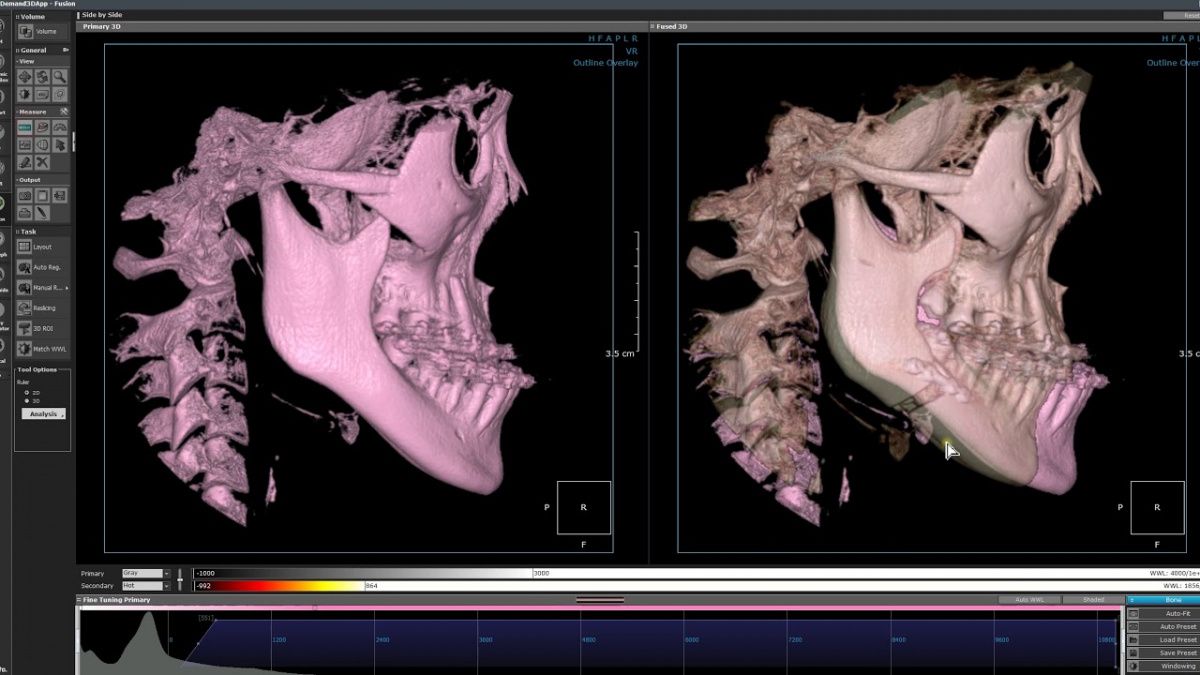

Немаловажным, а может главным вопросом, является универсальность программы-просмотровщика, в которой будут работать врачи-стоматологи. У Papaya 3D есть два варианта программ: Triana и OnDemand3D. Оба просмотровщика обладают схожим интерфейсом и имеют самые важные опции, а именно:

• 3D режим – показывает трехмерную модель челюсти с целью определения аномалий, деформация, а также визуализации виртуальных имплантатов.

Таким образом обе программы являются простыми в пользовании, но обладающими обширным спектром возможностей для диагностики любыми специалистами-стоматологами. В данные программы происходит загрузка классических файлов DICOM 3.0, которые являются общепринятым форматом записи данных пациента. Это важный момент, так как позволяют врачу, имеющему полную версию программы загружать даже сторонние исследования и просматривать их в этих программах. Простота в освоении этих программ позволяет даже специалисту, не работающему раннее с этими программами, быстро адаптироваться и получить качественную информацию. Возможность выгрузки STL-файла дополнительно создает возможность интегрировать данные с цифровым ортопедическим протоколом.